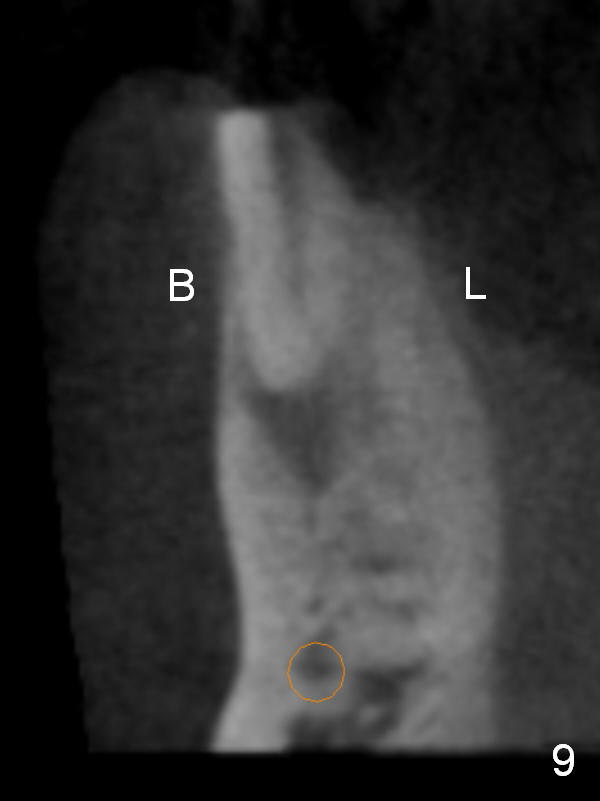

CT sagittal section shows that it is possible to place 4.5x20 mm implant (Fig.6). Axial (Fig.7) and coronal (Fig.9) sections show that the lingual (L) plate is much thicker than the buccal (B) one. To prevent the implant being buccally deviated, a Lindermann bur is used after extraction (black area in Fig.8,10) to remove ~ 1mm bone from the lingual plate (red area in Fig.8,11). A 2 mm pilot drill is placed as lingual as possible (green in Fig.8,11). If the implant (Fig.12) starts to deviate buccally while being placed, remove it from the osteotomy and remove more bone from the lingual plate. Place the implant again and monitor the trajectory tightly.